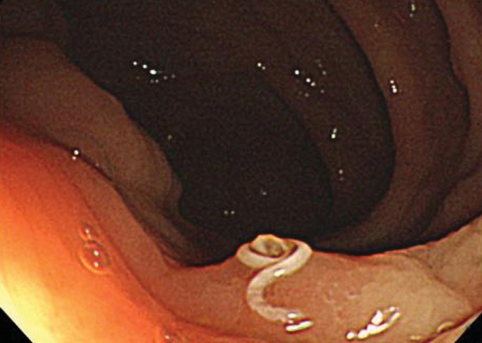

Colonoscopy revealed no abnormalities except for a small, white, worm-like object attached to the cecum. One end was embedded in the hyperemic edematous mucosa and the other end was coiled and movable within the lumen (Fig. 1A). Histologic examination of the cecal mucosa revealed a moderately dense eosinophilic infiltration in the lamina propria (Fig. 1B). Microscopic sectional evaluation of the retrieved parasite was consistent with T. trichiura (a male worm including a testis). He was treated with albendazole.